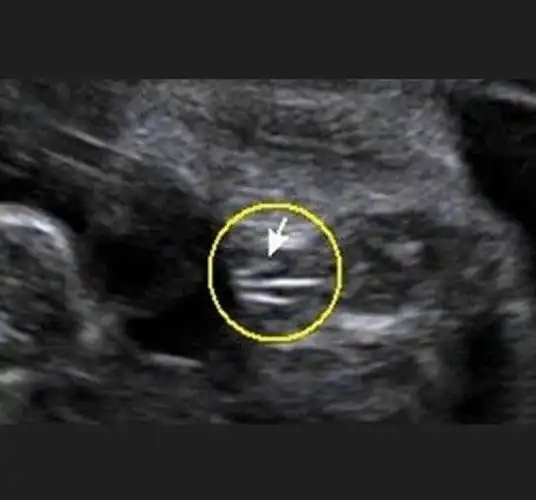

思维的看不懂,彩超的男孩是明显的小鸡鸡,女孩的是3条小白线!

给你看个图你就明白了…放大看两腿之间有三个点,三条白线,男宝是没有